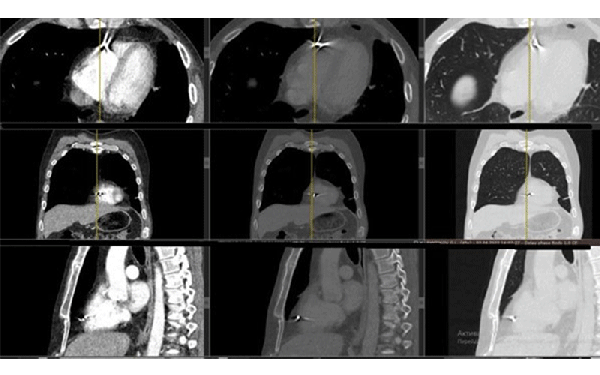

We are not a military hospital, but unfortunately, the number of wounded soldiers is currently so large that military medicine cannot cope with them and numerous civilian hospitals take over the treatment of wounded soldiers. Therefore, among ordinary civilian patients, we examine and treat wounded military personnel. In our hospital, these are mainly acubarotraumas, burns, gunshot wounds of the maxillofacial area, chest, abdominal organs, and of course most of all the trauma extremities.

From the first days we started to provide assistance to wounded civilians and the military from different parts of our country. Our work is to diagnose various injuries of the chest, abdomen, skull, pelvis and especially the limbs. We help thoracic, abdominal and facial surgeons, ophthalmologists, and especially orthopaedists in preoperative and postoperative stages of the treatment.

One of our tasks, as radiologists, has been to find foreign bodies in the people’s arms, legs, abdomen and thoracic wall with help of radiography or ultrasound. We also help in finding traumatic injuries to internal organs. Despite the lack of new equipment, we try to help all our patients as much as possible. Psychological support of patients is also important in our work, which I am doing.